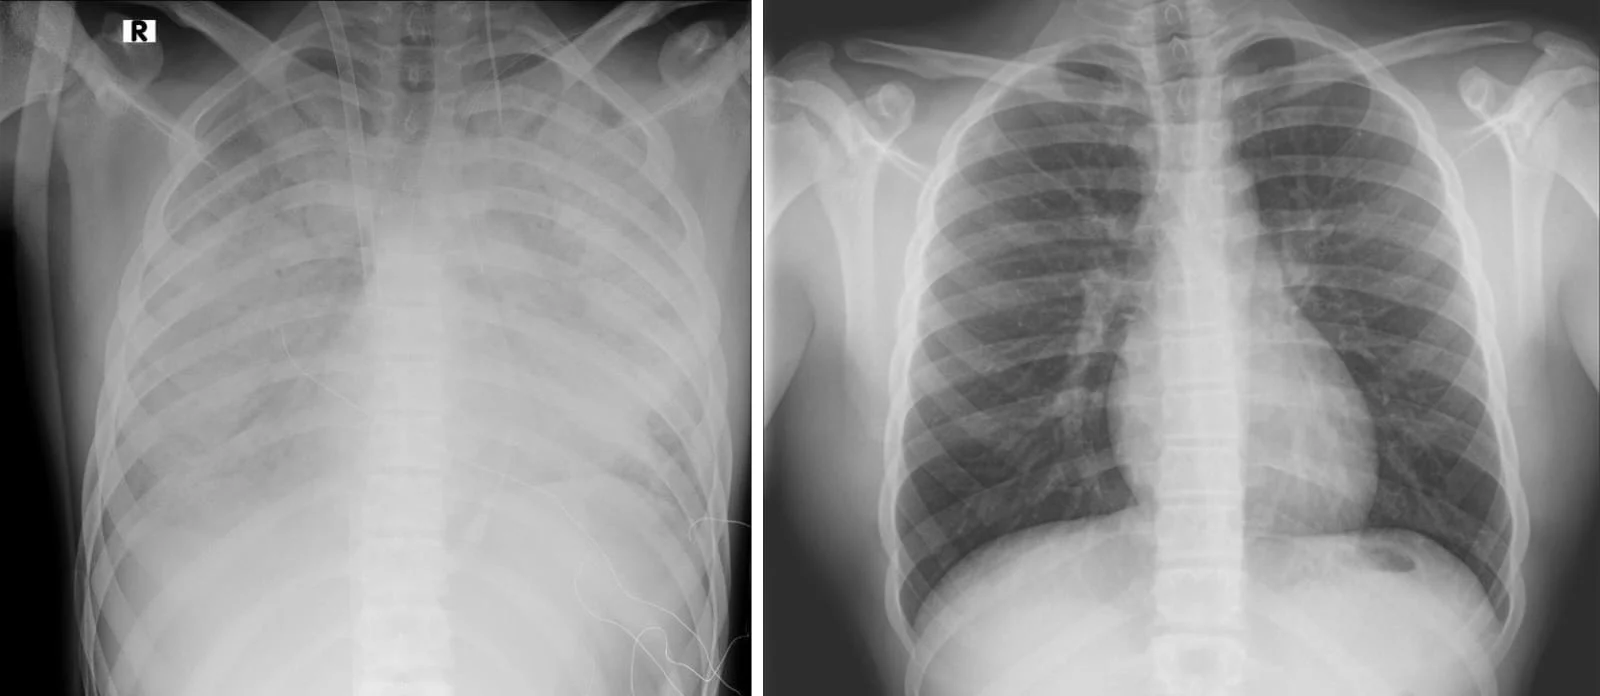

על פי נתוני משרד הבריאות, באמצעות סקר שנערך על ידי אוניברסיטת בר אילן, אחד מכל עשרה תלמידים בכיתה י' משתמש בסיגריה אלקטרונית - מגמה שהולכת וגדלה עם השנים. בניגוד למה שהיה מקובל לחשוב, הסיגריה האלקטרונית ממכרת לא פחות (חלק מהמומחים טוענים אף שיותר) מאשר סיגריה רגילה, וטומנת בחובה סכנות בריאותיות קשות.

לפי האגודה למלחמה בסרטן, בין תופעות הלוואי של השימוש בה ניתן למנות מיגרנות, דיכאון, חרדה, אין אונות, שבץ מוחי, סרטן חלל הפה, סרטן הריאה ועוד. רק היום נודע על נער בן 16 שאושפז במצב קשה בטיפול נמרץ בעקבות שימוש בסיגריות אלקטרוניות.